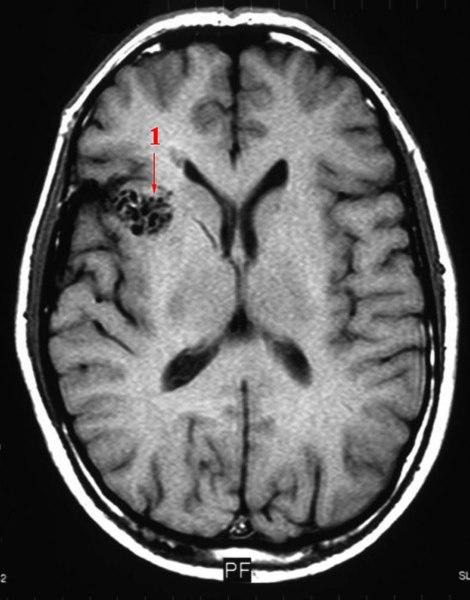

MR - tverrsnitt av en arteriovenøse malformasjon (AV malformasjon - 1). En unormal, direkte forbindelse mellom arterier og vener uten noe kapillærsystem i mellom. Forekommer særlig i sentralnervesystemet og er som regel medfødt. De fleste AV-malformasjoner er uten symptomer, men de kan også føre til smerter eller blødning eller føre til andre alvorlige medisinske problemer.